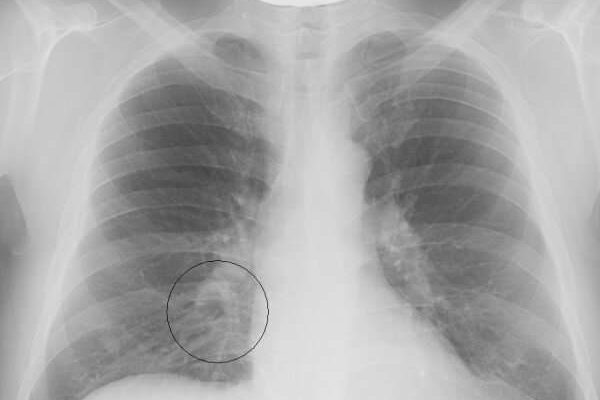

Выделение патологии в отдельную группу оправдано тем, что она имеет специфические диагностические, клинические и прогностические свойства. Этот тип пневмонии сложно визуализировать на рентгеновских снимках, потому что локализация похожа на корень легкого.

Наличие пневмонии в организме ребенка можно подтвердить только после рентгенологического исследования и проведения лабораторных исследований. Если диагностирована колющая пневмония, необходим дифференциальный диагноз, чтобы отличить эту патологию от туберкулеза и онкологии бронхов.

- Рентген. На фото виден затемненный участок.